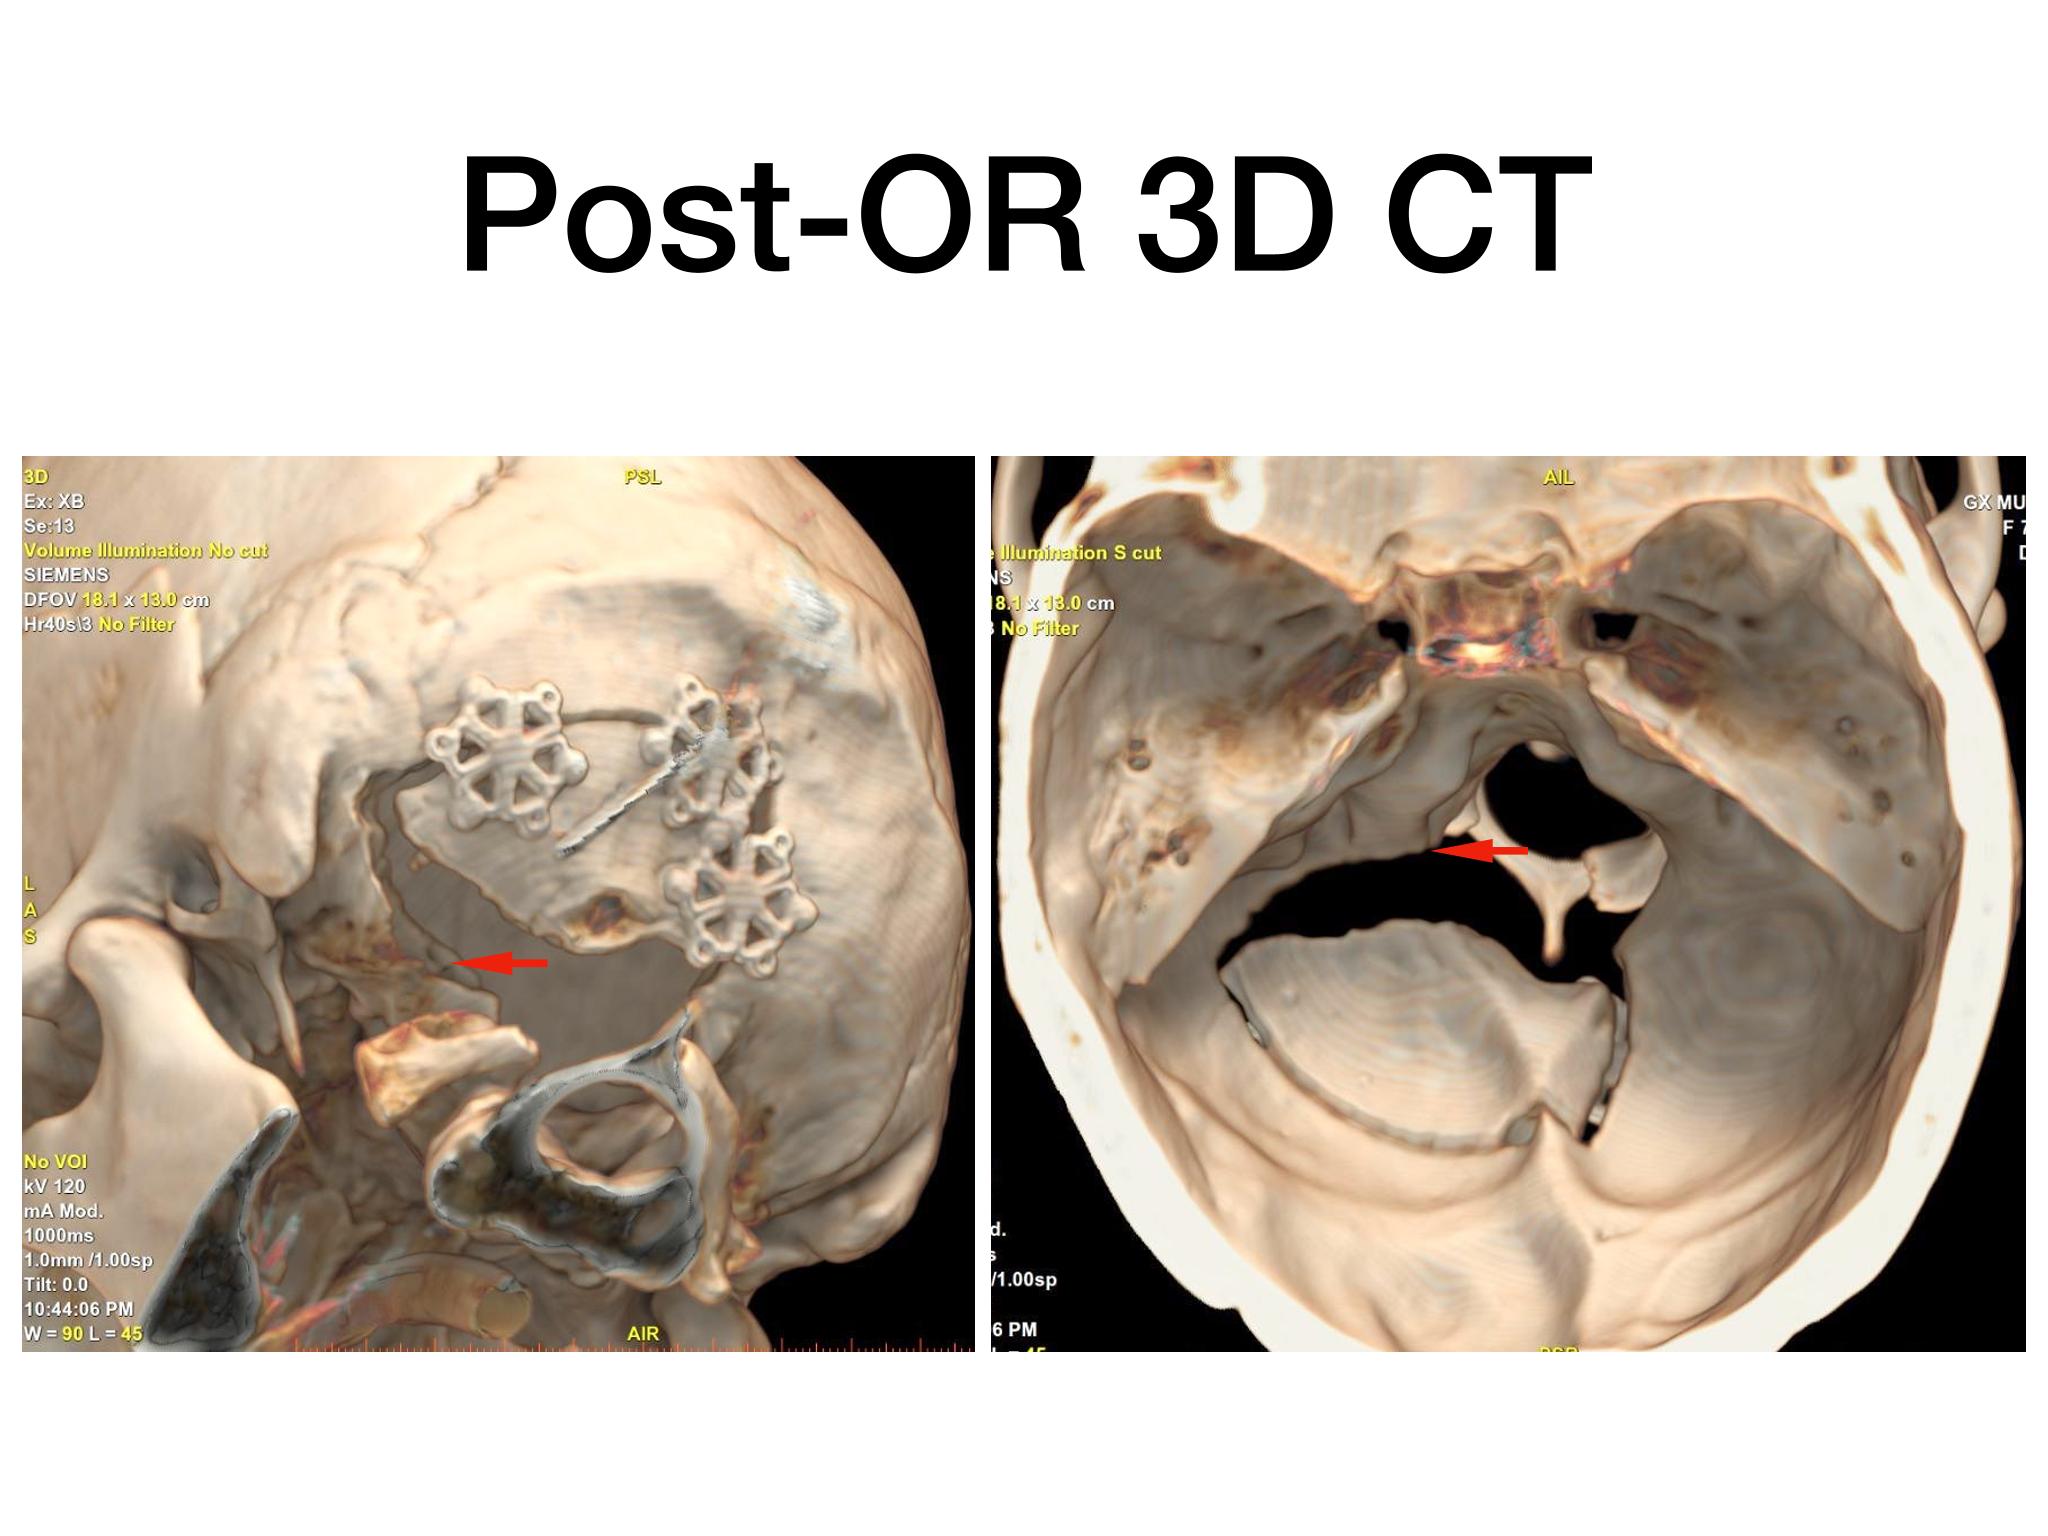

汇报一例后颅底肿瘤手术。为枕骨大孔巨大腹侧型脑膜瘤,该患者高龄,同时合并肺Ca,术前2周急性加重,枕骨大孔疝前期表现,术前已有延髓压迫及后组颅神经麻痹表现。经详细评估后采用远外侧经髁窝入路,最大化显露,重点保护延髓、后组颅神经,尽可能“零骚扰”。术中肿瘤质地韧,血供一般,与肿瘤上极与后组颅神经黏连紧密,最终99%切除,残留约1%,术后顺利康复出院,无新发症状,为后续进行肺部病变化疗创造有利条件。